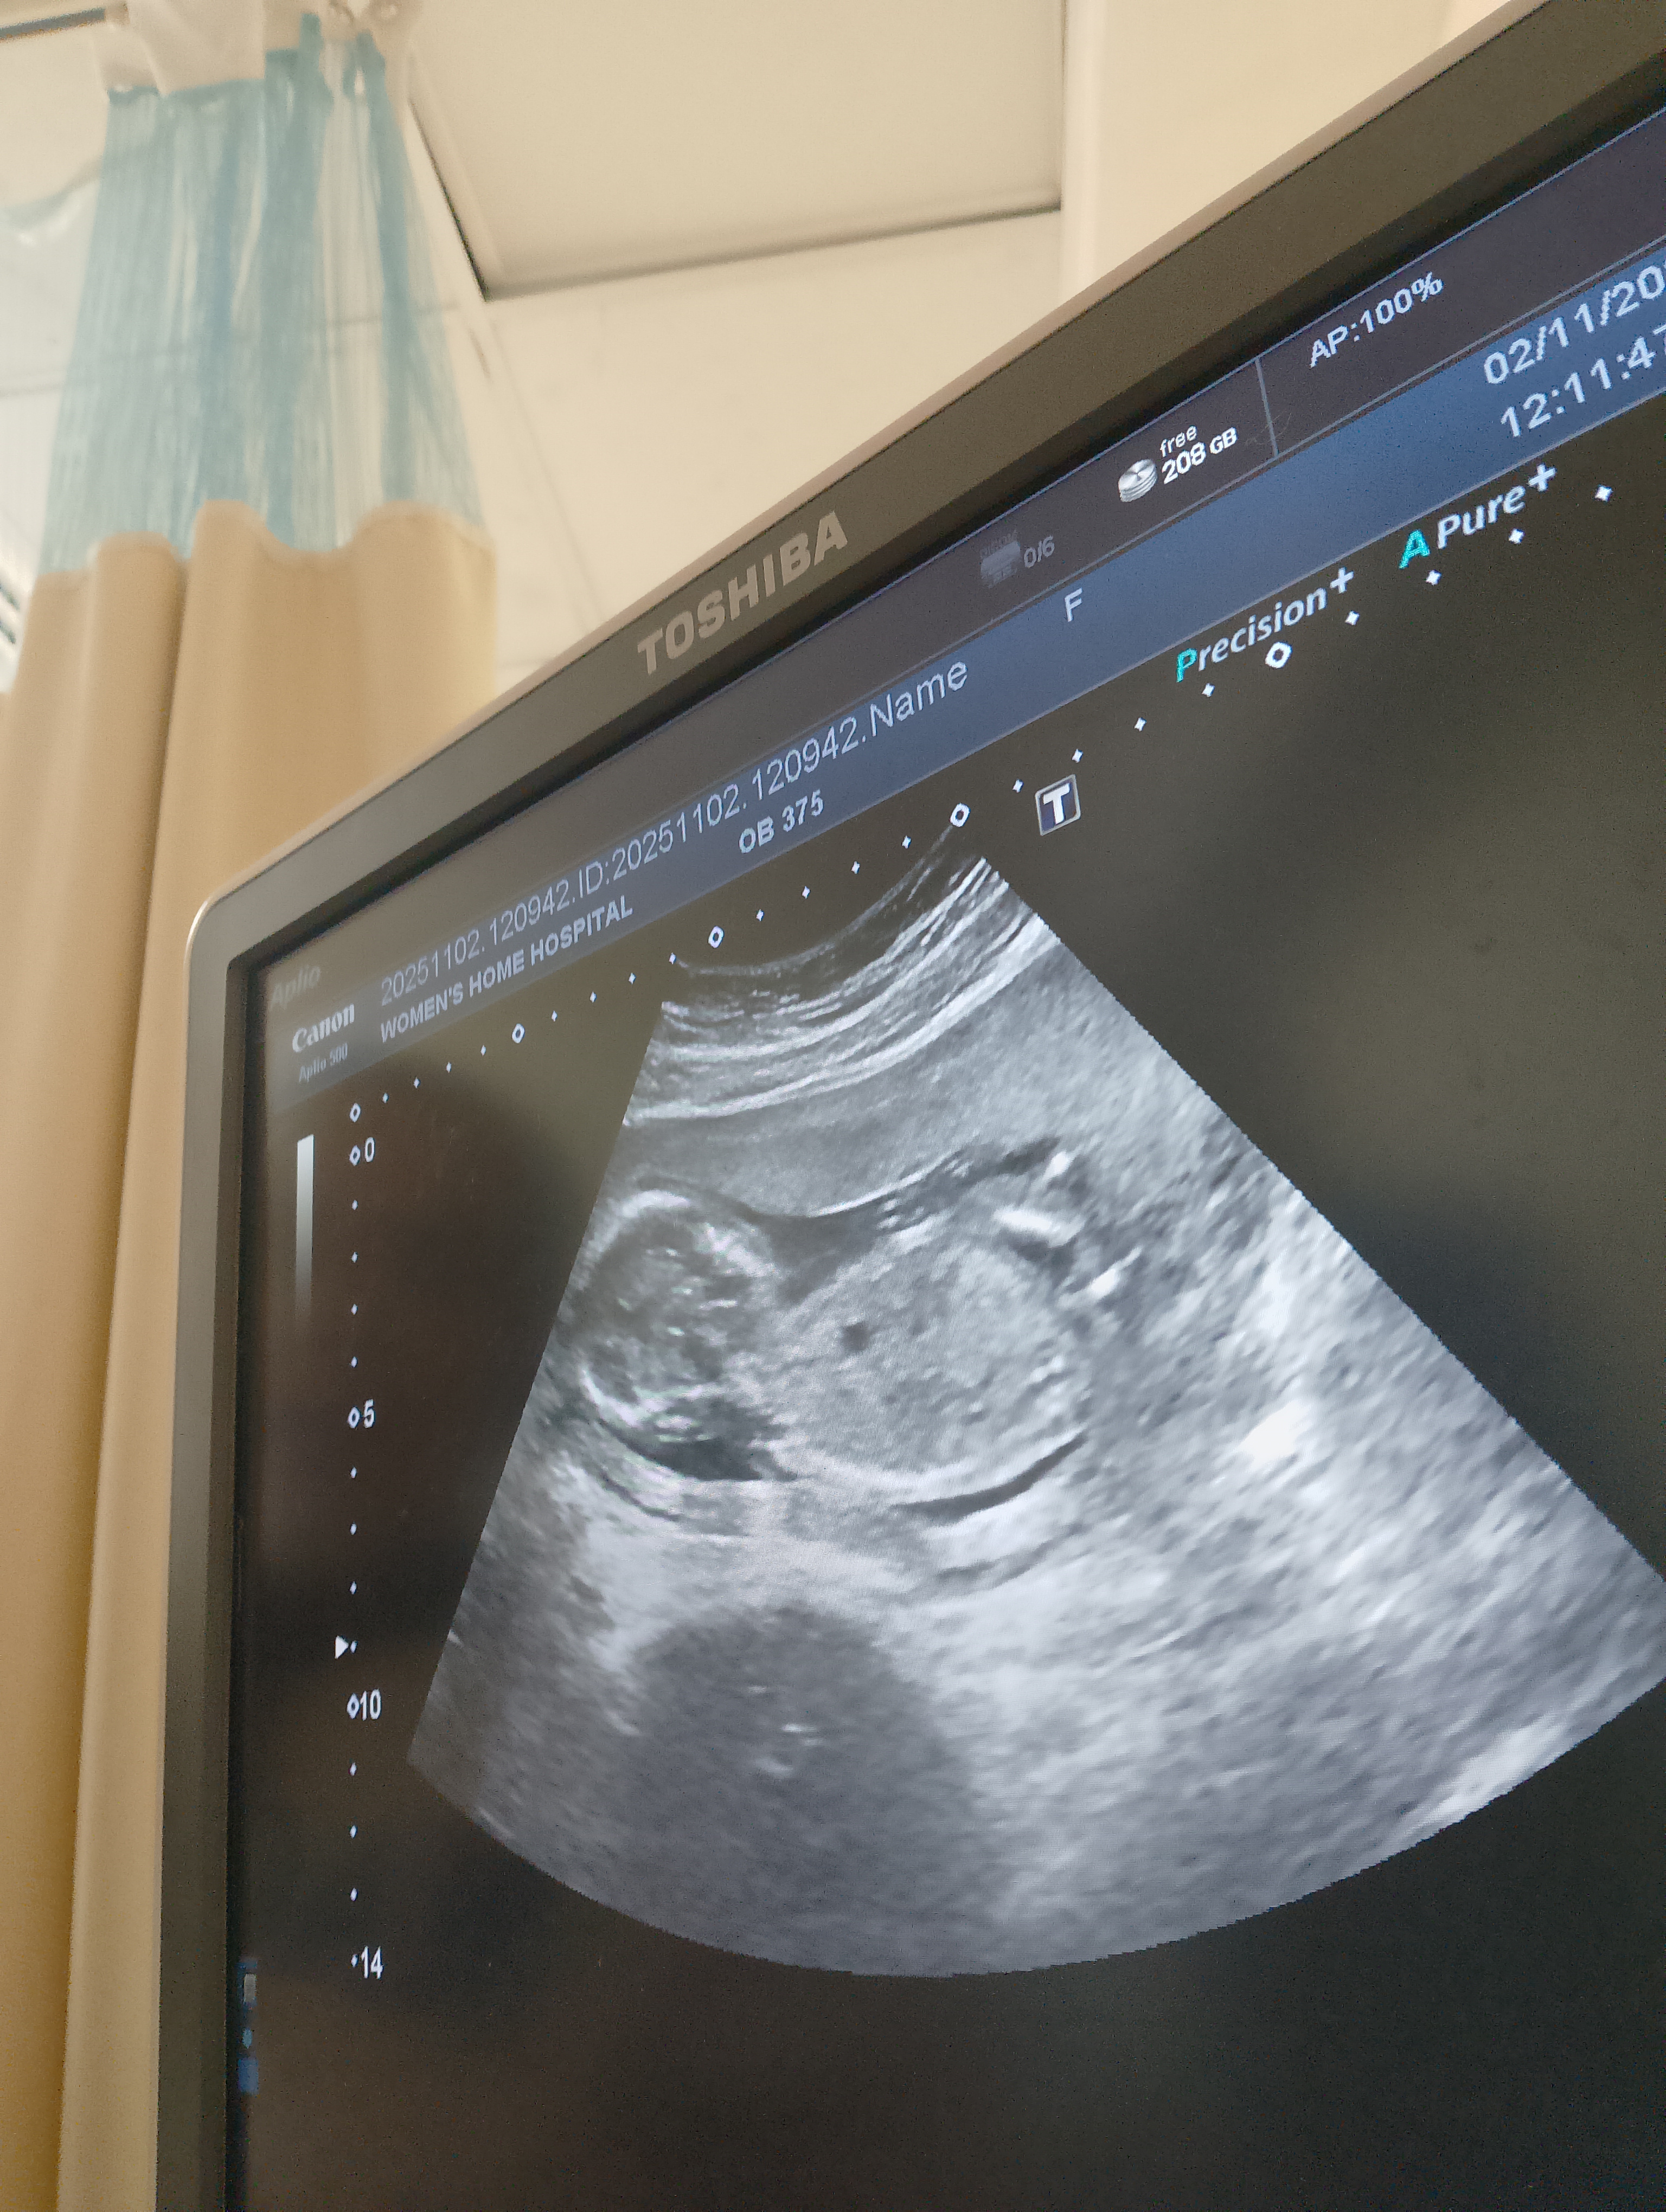

من فضلكم رحت المستشفي محدش فادني عايزة أعرف دا ولد ولا بنت

الاسبوع 17